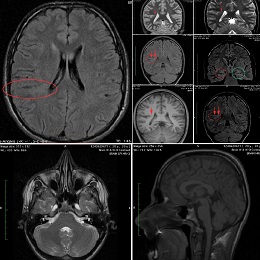

This recent MRI exam WITHOUT Contrast in IHC, revealed a subtle congenital malformation of cortical development within right parietal lobe.

Final IMPRESSION is:

A subtle linear band intensity extending between deep posterosuperior aspect of right Sylvian fissure and posterior aspect of corpus of right lateral ventricle (isointense with gray matter on all sequences). These MRI findings strongly suggest "Type II (Taylor type) focal cortical dysplasia (transmantle cortical dysplasia)" or "transmantle gray matter heterotopia". Virtually, they may be representing two different names for the same entity.

Secondary hippocampal sclerosis is identified, bilaterally (secondary to long-term intractable epilepsy).

Good news is, this congenital malformation has an excellent prognosis following a competent surgical excision of the malformed area, and a "completely seizure-free life" may be granted subsequently. Depending on clinical results, this young patient may no longer be dependent on life-time anti-epileptic medications.